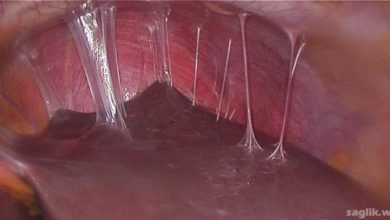

İnterstisyel Sistit Nedir? Belirtileri, Nedenleri, Tedavisi

İnterstisyel sistit (interstitial cystitis), mesane veya pelvik bölgede rahatsızlık ve / veya ağrıya neden olan kronik (uzun süreli) bir mesane…